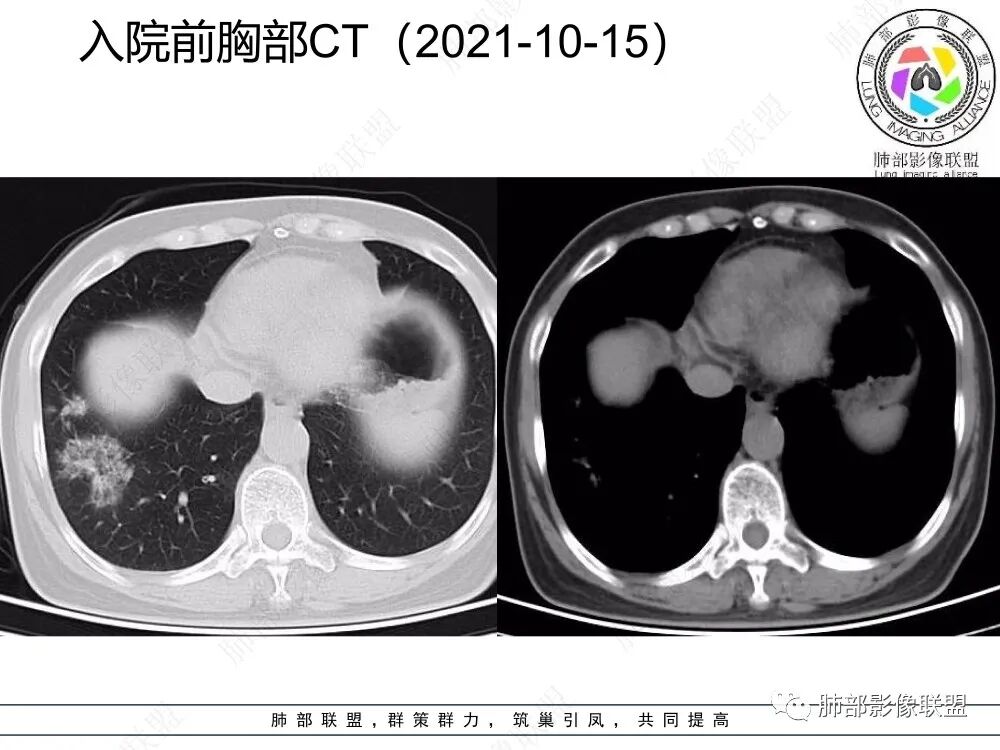

2、CT表现为两肺下叶结节影、斑片影、磨玻璃影,沿支气管血管束分布,部分支气管壁显示增厚。粗略一看部分病灶内似可见“细网格影”,但是仔细观察,可发现此“细网格影”不同于我们常见的“细网格影”,尤其是右肺下叶病灶,可以观察到病灶内部的网格上有高密度结节感或颗粒感,部分层面见“反晕征”,且反晕的边缘亦可观察到结节感。未见胸腔积液。

3、反晕征又称为环礁征、环岛征或环状珊瑚岛征,表现为中心磨玻璃影,周围为高密度影环绕,最初被认为是隐源性机化性肺炎(COP)的特征性表现之一,但随后不断有研究发现反晕征亦可出现在多种感染及非感染性疾病、肿瘤及非肿瘤性疾病中。反晕征的常见疾病谱有:①感染性疾病:肺孢子菌病、侵袭性肺真菌感染、肺结核、病毒性肺炎;②非感染性疾病:肺淋巴瘤样肉芽肿、韦格氏肉芽肿、 结节病、机化性肺炎(包括隐源性和继发性)、肺栓塞;③肺腺癌以及肺肿瘤治疗后。

4、本例急性病程,发热、咳嗽,结合影像多发磨玻璃影表现首先会考虑到感染性病变:①病毒性肺炎,病灶间质分布为主,常较弥漫,外围多见,临床症状重且常与影像表现同步;②支原体肺炎,病变多为1-2叶段、少数多叶段分布,支气管壁弥漫较均匀增厚,可见树芽征、腺泡结节及树雾征;③肺结核,上叶尖后段及下叶背段多见,多灶性、多态性,树芽征,可有空洞、钙化等;④机化性肺炎,病变胸膜下和支气管血管束分布,可有实变、结节及反晕征。

本例病变以两肺下叶为主,非结核好发部位,通常会想到感染性病变,右肺下叶病灶高密度结节感、反晕征,较为符合继发性肺结核(间质浸润为主),但双肺散落的相对柔和淡薄小片影给诊断带来困惑。

2、但影像学具有一定的特征性,病变一般沿支气管树分布或小叶分布,一般上肺多于下肺。部分病例呈双肺“雪花样”分布,较有特点。部分病例可表现为“反晕征”。除以上表现外,间质性肺结核还可以表现为:1 肺小叶间质内异常,表现为小叶间质内网状影,呈网结节样改变,与正常肺分界较清晰是其特点。2 支气管血管束增粗和小叶间隔增厚。3 磨玻璃影。

2、好发部位与其它结核类似,上叶及下叶背段为主。 3、烟花征,反晕征,环呈结节状,可以伴随空洞,树芽征,结节灶,胸水。(反晕征:一般周围实性环形高密度影,中央呈低密度;一般环超过圆的3/4,结核的环主要是小叶核心结节组成,类似于多发树芽征聚集,边缘结节感。中央的晕:可以是腺泡结节,树芽征,细网状,磨玻璃影,很少正常,主要成分是小叶内间质增厚、小叶核心结节、肺泡内病变。)其实也体现了结核的多灶性、多态性特点。